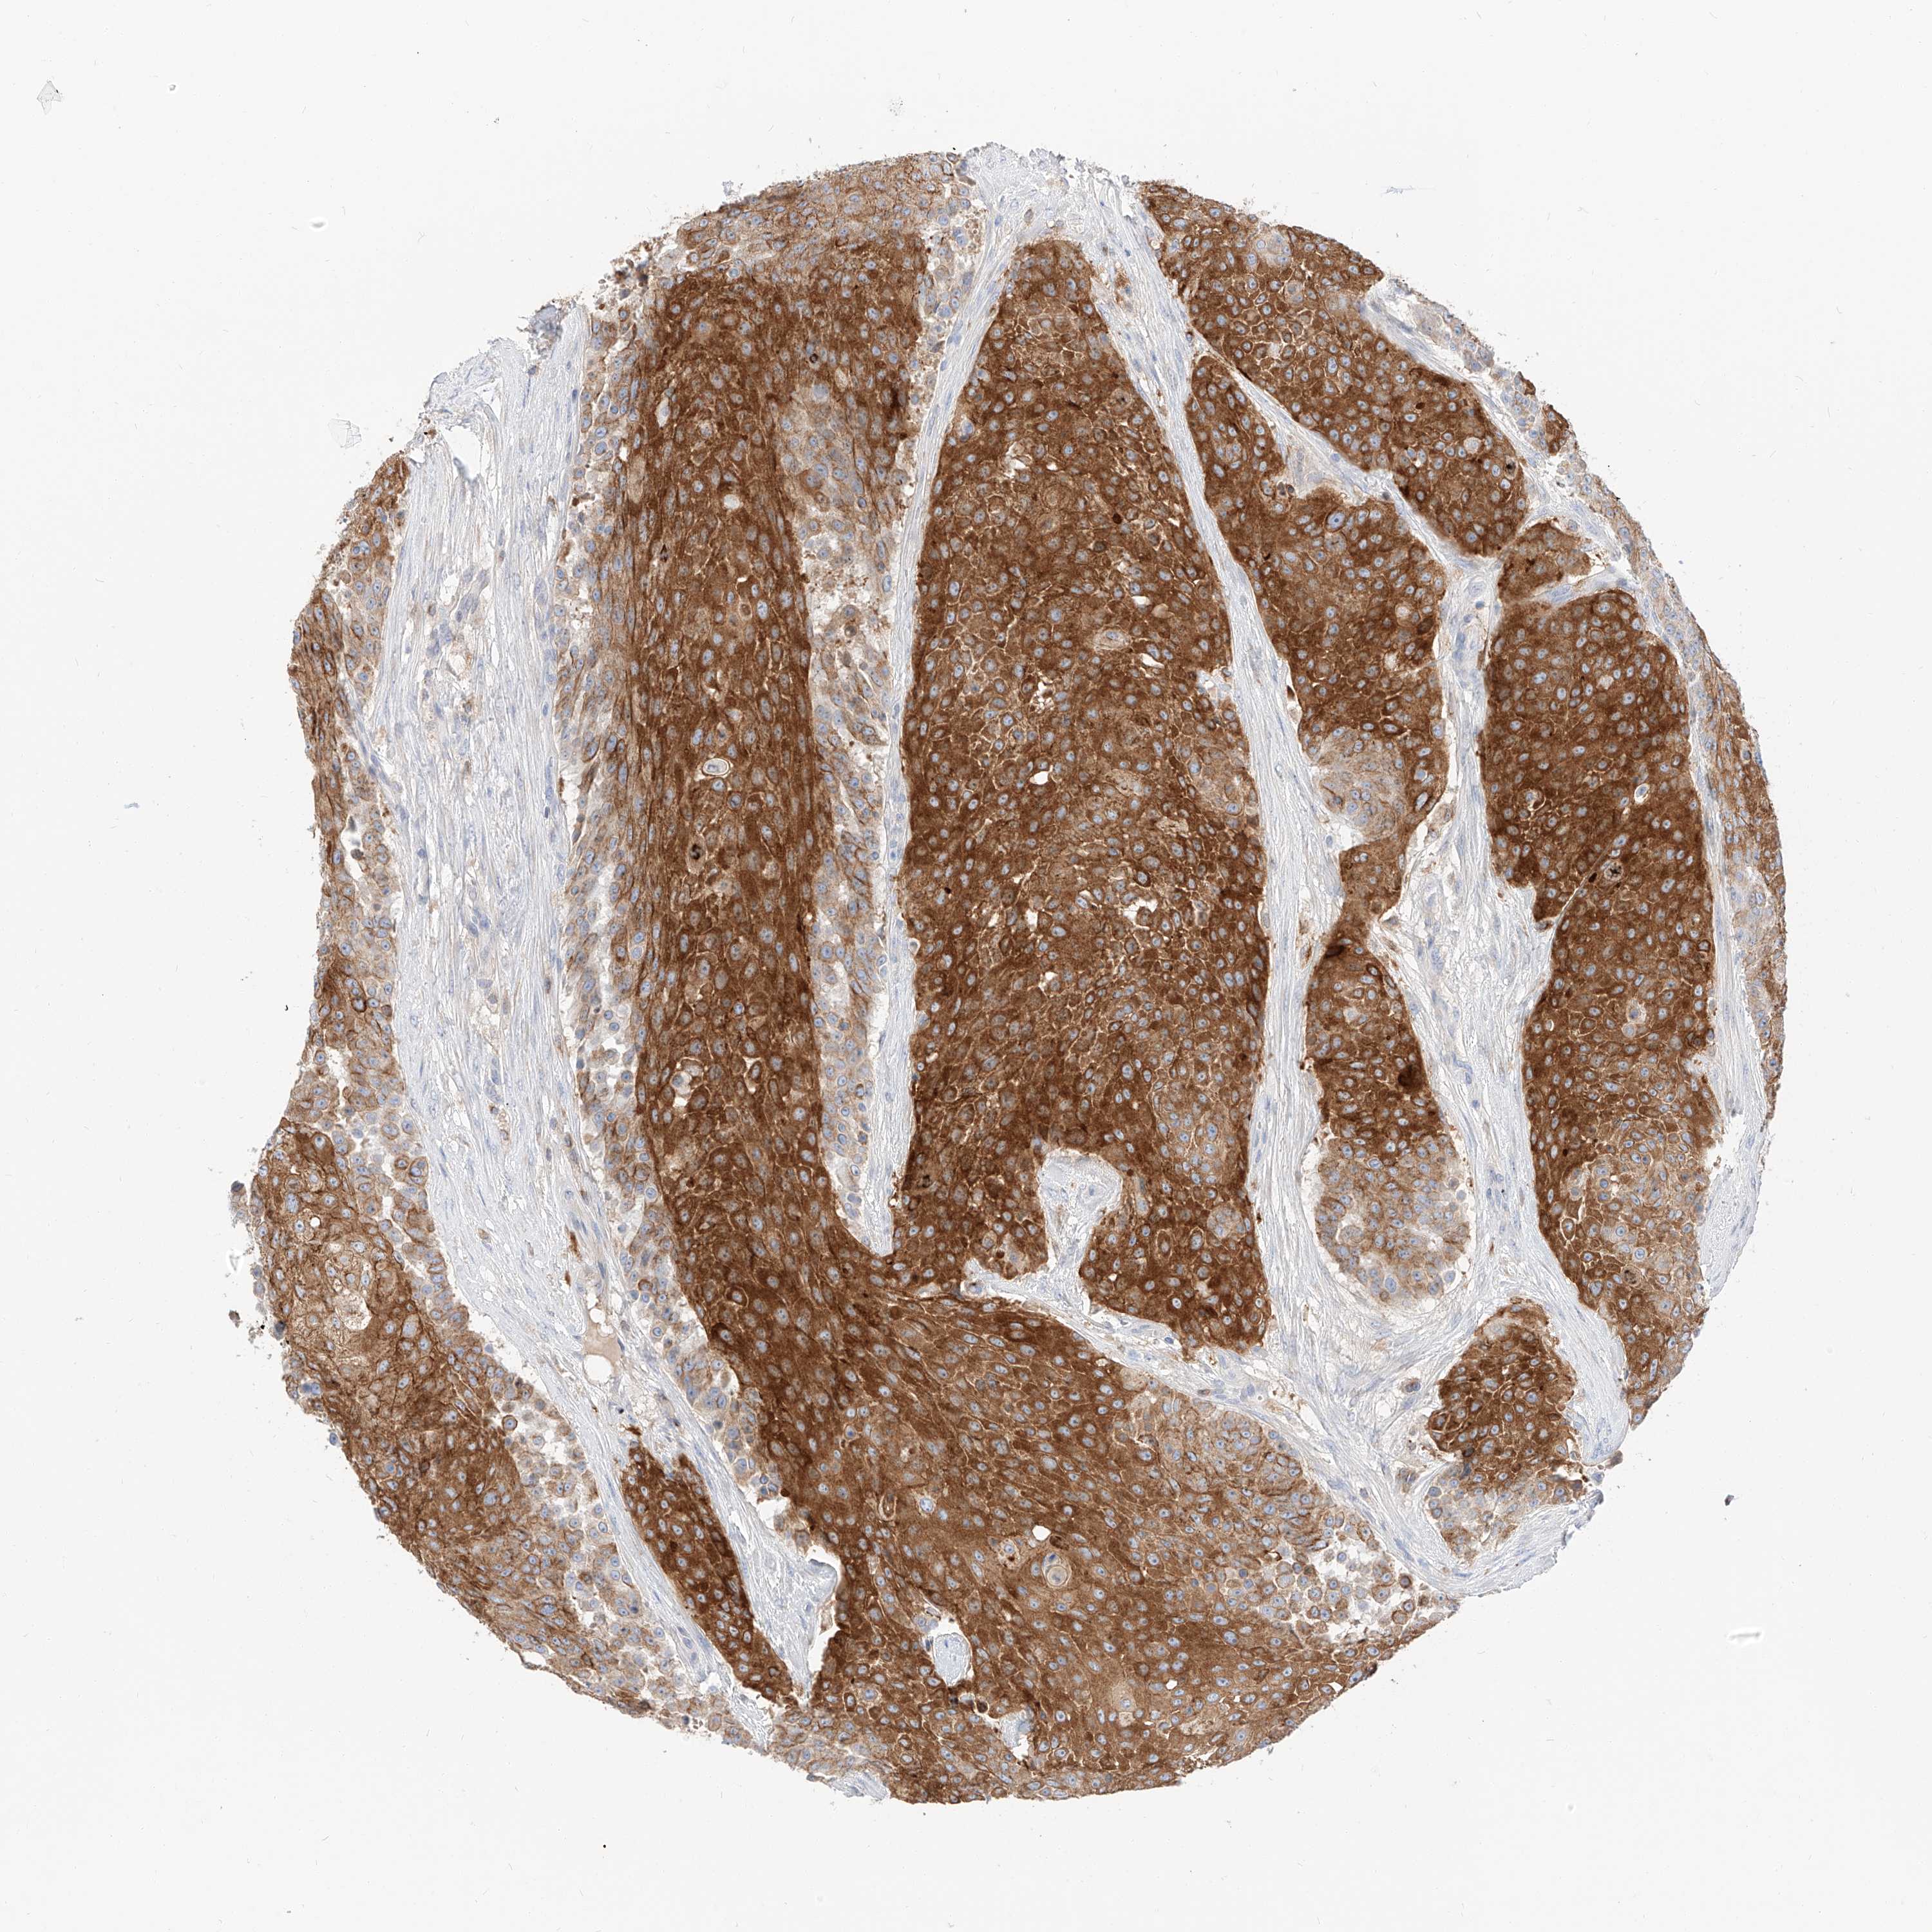

UROTHELIAL CANCER - Protein expressioni

A mouse-over function shows sample information and annotation data. Click on an image to view it in a full screen mode. Samples can be filtered based on level of antibody staining by selecting one or several of the following categories: high, medium, low and not detected. The assay and annotation is described here.

Note that samples used for immunohistochemistry by the Human Protein Atlas do not correspond to samples in the TCGA dataset.

Antibody stainingi

Antibody staining in the annotated cell types in the current human tissue is reported as not detected, low, medium, or high, based on conventional immunohistochemistry profiling in selected tissues. This score is based on the combination of the staining intensity and fraction of stained cells.

Each image is clickable and will lead to virtual microscopy that enables deeper exploration of all samples and also displays staining intensity scores, fraction scores and subcellular localization as well as patient and tissue information for each sample.

Antibody HPA029712

Antibody HPA029713

Staining

High

Medium

Low

Not detected

Intensity

Strong

Moderate

Weak

Negative

Quantity

>75%

75%-25%

<25%

None

Location

Nuclear

Cytoplasmic/membranous

Cytoplasmic/membranous,nuclear

Urothelial carcinoma, Low grade

Urothelial carcinoma, High grade